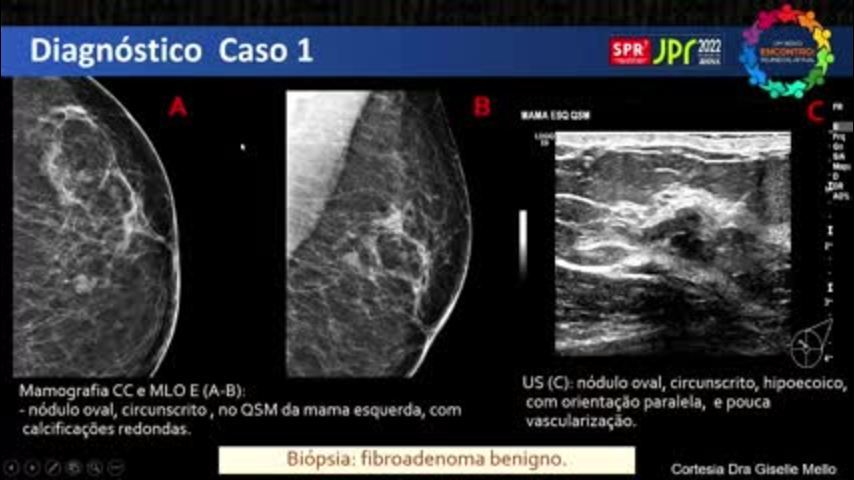

Casos Difíceis e o Que Aprendi com Eles - Caso 1